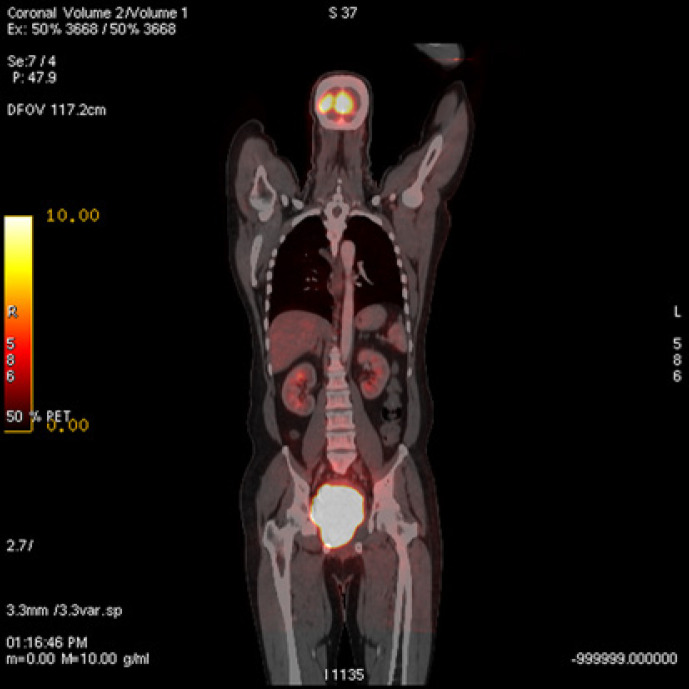

For the purpose of appropriate staging, positron emission tomography (PET) was done 25 days after the CT scan, and a large soft tissue mass (142 mm CC × 99 mm AP × 88 mm RL) was noted in the rectum and anal canal showing intense FDG uptake (SUV max 35) and the mass abutting the urinary bladder and prostate (Fig. 8, 9, 10), suggesting immunohistochemically proven lymphoma. A hypervascular focal lesion in the right hepatic lobe without appreciable FDG uptake was suggestive of hypervascular hemangioma. No other appreciable suspicious lesion or abnormal FDG uptake elsewhere in the body was seen. Due to uncontrolled bleeding and as it took more than a month to confirm the diagnosis, he was planned to start urgent radiotherapy. EBRT was urgently started with Cobalt 60 with 1.25-MV photon energy (Best Theratronics) using a 2-D technique. Initially, 12 Gy in 4 fractions was given as hypofraction to control the bleeding immediately, followed by 28 Gy in 14 fractions, i.e. 40 Gy in 18 fractions, 5 fractions/week in 25 days without any delay or gap correction. The patient was treated with adjuvant chemotherapy with a standard R-CHOP protocol and completed 6 cycles. Post-EBRT DRE revealed minimal scaring in the anorectal region with significant regression of growth. Post-chemotherapy PET evaluation done 8 months after diagnosis showed irregular wall thickening with inhomogeneous enhancement and narrowing of lumen along the anorectal region. The scan showed an interval decrease in FDG avidity (SUV max 3.5 vs. 35 before) without any activity elsewhere in the body (Fig. 11, 12, 13). Since the completion of chemotherapy he has been followed up for more than 30 months and was still disease free at a follow-up with a further MRI/PET scan.

Fig. 10.

Pretreatment PET-CT scan: coronal image.

Fig. 13.

Posttreatment PET-CT scan: coronal image.

For the staging purpose, the imaging is the best modality to see the extent. CT of the chest and abdomen and pelvis is recommended, and PET is the best modality with conventional CT for proper staging. PET scan can detect marrow infiltration, though bone marrow aspiration remains the gold standard. In our case, the CT scan of the abdomen and pelvis showed an exophytic rectal mass originating, from the outer wall of the rectum compressing the lumen (measuring 67 × 84 mm) extending towards the urinary base. No distant or nodal involvement was seen, and there was no ascites. The chest X-ray posterior anterior view also suggested normal findings. CEA was 1.99, and LDH was not elevated. But 25 days after the initial CT scan, its aggressiveness was shown on a PET scan that showed almost double of the initial growth size (142 mm CC × 99 mm AP × 88 mm RL vs. 67 mm × 84 mm) (Fig. 1,2,8−10).